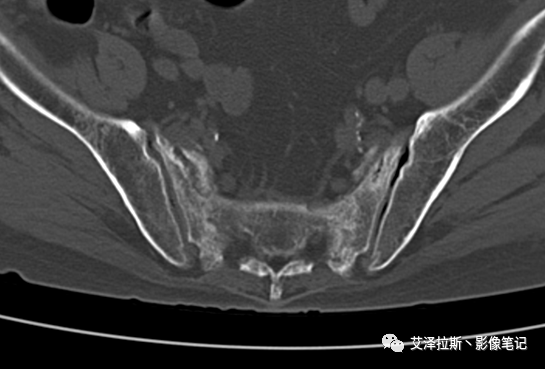

病例2:患者,女性,69岁,老年性骨质疏松症。

CT平扫:

X线、CT:骶骨重度骨质疏松,双侧骶骨翼皮质断裂,分别见迂曲走行的纵行透亮线位于骶孔外侧,大致与骶髂关节间隙平行,骨折端局部可见骨痂、骨质硬化。

骶骨功能不全骨折

①单侧或者双侧骶骨翼骨折,典型者呈“H”形,即“Honda征”;

②骨折线位于骶孔外侧(如下图,主要发生于1区),通常可能会伴随耻骨的功能不全骨折(如:病例2 右侧耻骨上支骨折,L5双侧横突骨折);

③愈合期骨折线模糊,骨痂形成,骨质硬化;